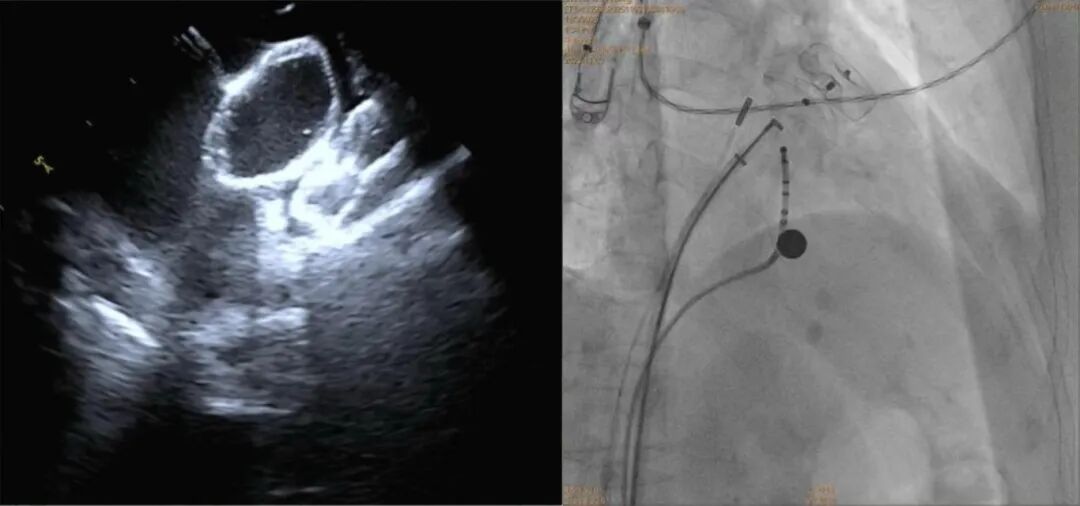

手术在导管室、麻醉科、超声科等多科室协作下进行。团队经股静脉穿刺,在三维标测系统引导下完成房颤射频消融,随后在X线及心腔内超声指导下植入左心耳封堵伞,成功闭合左心耳开口。整台手术历时约两小时,患者房颤转复为正常窦性心律,术后恢复良好,胸闷、心悸症状明显改善。